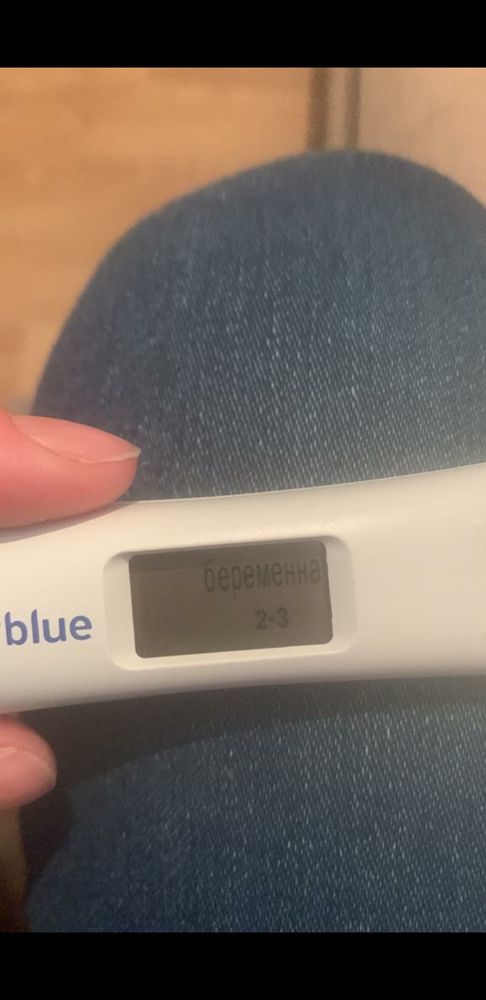

Лимоночка, Получается что этот тест от 11.01.23 показывает верно, просто где-то прочитал что Clear Blue Digital не точно показывает.

Лимоночка, Получается что этот тест от 11.01.23 показывает верно, просто где-то прочитал что Clear Blue Digital не точно показывает.

Gennady Babansky, этот тест показывает результат по уровню хгч, 2-3 недели эмбриональных это 4-5 акушерских как раз. А правильно или нет не знаю, думаю погрешность есть, но в целом наверное верно

Кстати когда она сделала этот тест 11 января, который показал что больше 2ух недель уже, а 13 Января уже в поликлинике врач что-то нащупала рукой в боку у неё она говорила и сказала что ну вот он, что-то такое

Лимоночка, Нашлась фотография это было 9 января, плохо видно правда, посмотрел в интернете динамику тестов это вроде как 13-15 дпо

А этот 11 января вечером

А этот 11 января вечером

В большинстве случаев все так и говорят что зачатия и тд в декабре было, а начинаешь смотреть учебники, приложения по беременности (каркуляторы и тд) ютуб видео и начинает рисоваться другая картина, что типа вот допустим если бы зачатие было 1го то до 16 января ещё 15 дней грубо говоря, и вот около 5 дней она добирается по трубам, потом крепится и растёт, как пишут 1 мм в день, и так совпадает что увидели 16 января, пя 7,5 мм. Тест на беременность был 11 января клеар блу диджитал показал 2-3 недели, 9 января 2 плоски яркие обычный тест, но оба теста делались вечером, не утром, 13 января врач гинеколог что-то нащупала в боку, типа вот есть там что-то, я понимаю я спрашиваю одно и тоже постоянно у всех и получаю разные но более менее хорошие и обнодежиаающие ответы что это декабрь, спасибо за это людям больше, мне кажется что у меня паранойя уже начинается, я очень сильно хочу чтобы всё было так как Вы пишите что это 25 декабря! В некоторых случаях мне говорили что овуляция могла быть позже и что после овуляции можно забеременеть, вот поэтому наверное переспрашиваю всё, извините если что!

А имеет ли значение в какое время делается тест на беременность утром или вечером, тесты просто делались вечером и вот тот который Clear Blue Digital показал 2-3 недели 11 Января, а знакомая сказала что он реагирует на уровень хгч и что сегодня он может показать 1-2 недели, а типа завтра утром уже 2-3(

Марина, Вот ещё пишут про тест Clear Blue Digital, как Вы считаете может такое быть?

Вот эти тесты один 9 Января вечером, другой 11 января и тоже вечером

Вот эти тесты один 9 Января вечером, другой 11 января и тоже вечером

Елена Ивановна , 9 января уже судя по тестам 15 дпо точно было,вот мои тесты хгч -475 и 15 дпо

Понятно вообщем, а Вы не знаете Clear Blue Digital, точно показывают?